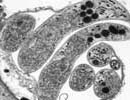

Cryptosporidium hominis UKH1

Courtesy of Saul Tzipori, Tufts

| Comment: | Cryptosporidium hominis is the dominant species which infects humans. Although generally self-limiting, this disease can cause fatalities in children and immunocompromised adults. The genome sequence of Cryptosporidium hominis shows features consistent with its life cycle as an obligate parasite. This organism lacks the genes necessary for the production of a number of biochemical building block such as nucleotides and amino acids. To compensate for this lack, the genome contains a large number of transporter or transporter-like genes. |